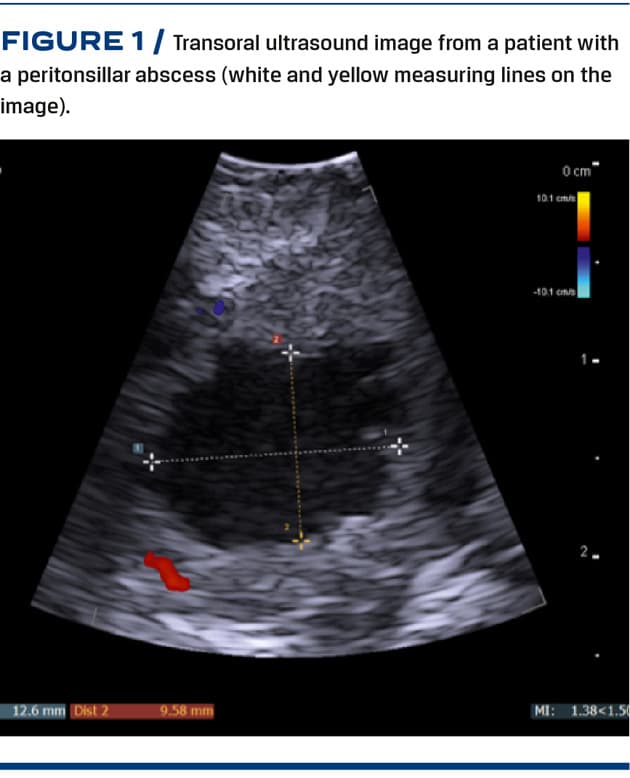

The otorhinolaryngologist on call will perform a standard oral examination, apply topical anaesthetics to the posterior pharynx and subsequently conduct a transoral ultrasound examination using a bk5000 machine and a Burr-Hole N11C5s transducer from BK Medical. The transducer is placed in a surgical glove filled with ultrasound gel. The tip of the transducer is then placed on the palatoglossal arch and swept from the cranial to the caudal end of the affected tonsil. An abscess is expected to appear as a hypoechoic area with ill-defined margins. If an abscess is not clearly visualised, the slightly larger high-frequency Hockey Stick X18L5 transducer may be applied to obtain a higher resolution image. If an abscess cavity is suspected, local anaesthesia is injected into the mucosa, and an ultrasound-guided needle aspiration is attempted. The aspiration technique chosen will depend on the degree of trismus and the severity of the gag reflex. The needle aspiration will therefore either be performed with an in-plane needle guide attached to a Burr-Hole N11C5s transducer, (b) an ultrasound-guided free-hand technique or (c) a “blind” aspiration guided by the previously visualised abscess on the static ultrasound image, see Figure 1. If the initial aspiration is unsuccessful, up to two additional attempts may be made. If no abscess cavity is visualised, no needle aspiration is attempted. Instead, the patient is handled like the patients in the control group after three unsuccessful needle aspiration attempts.